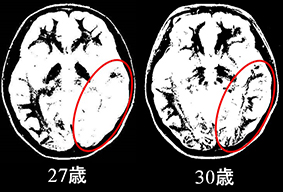

上図は、実際に最近活動している脳内ネットワークを示す、弊社の国際特許技術による独自の「枝ぶり画像」です。赤丸で示す部分は、27歳の時には白く描写され、ネットワークが弱い状態です。それが、30歳になるにつれて、しっかりしたネットワークとして黒く描写され、ほぼ左右対称に脳のネットワークが形成されてくる様子が見て取れると思います。

この画像が示すように、脳からみて全体のネットワークが整ってきたと判断できるのは、おおよそ30歳に差し掛かったあたりからなのです。